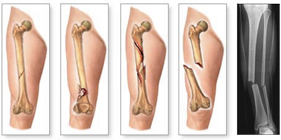

Questo tipo di fratture che, quindi, necessitano di una fissazione chirurgica verranno rese stabili da mezzi di sintesi diversi; si parla in questo caso di osteosintesi.

Durante l’intervento di osteosintesi i frammenti ossei vengono riallineati con appositi strumentari e vengono fissati con fili metallici, viti, placche, chiodi, fissatori esterni, ecc.

Ognuno di essi presenta specifiche peculiarità che ne determinano vantaggi e svantaggi. La scelta del mezzo di sintesi viene fatta dal Chirurgo in base a molteplici considerazioni (tipo di frattura, condizioni del paziente, qualità dell’osso). La maggior parte dei mezzi di sintesi è costituita da leghe metalliche, generalmente il titanio, che sono perfettamente biocompatibili. Essi possono, pertanto, rimanere in situ senza creare particolari problemi. Nei pazienti giovani o nel caso in cui i mezzi di sintesi diano fastidio perché troppo superficiali o perché determinano limitazione del movimento, si tende a rimuoverli dopo un tempo adeguato dalla guarigione (in genere dopo circa 18-24 mesi dalla frattura).

Nuovi strumentari e tecniche chirurgiche permettono l’osteosintesi mininvasiva che ha il grande vantaggio di limitare al massimo l’esposizione chirurgica e quindi accelerare la ripresa funzionale.